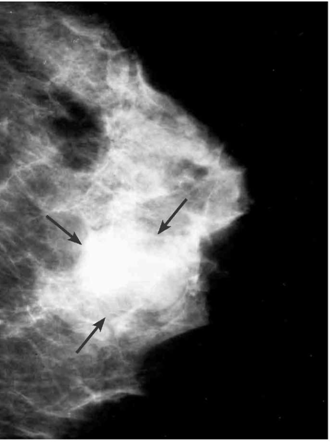

בממוגרפיה ניתן לראות גוש הסמיך יותר מסביבתו, שגבולותיו חדים ומופרדים מרקמת השד. קשה להבדיל גוש זה מגוש סולידי (תצלום 12.12).